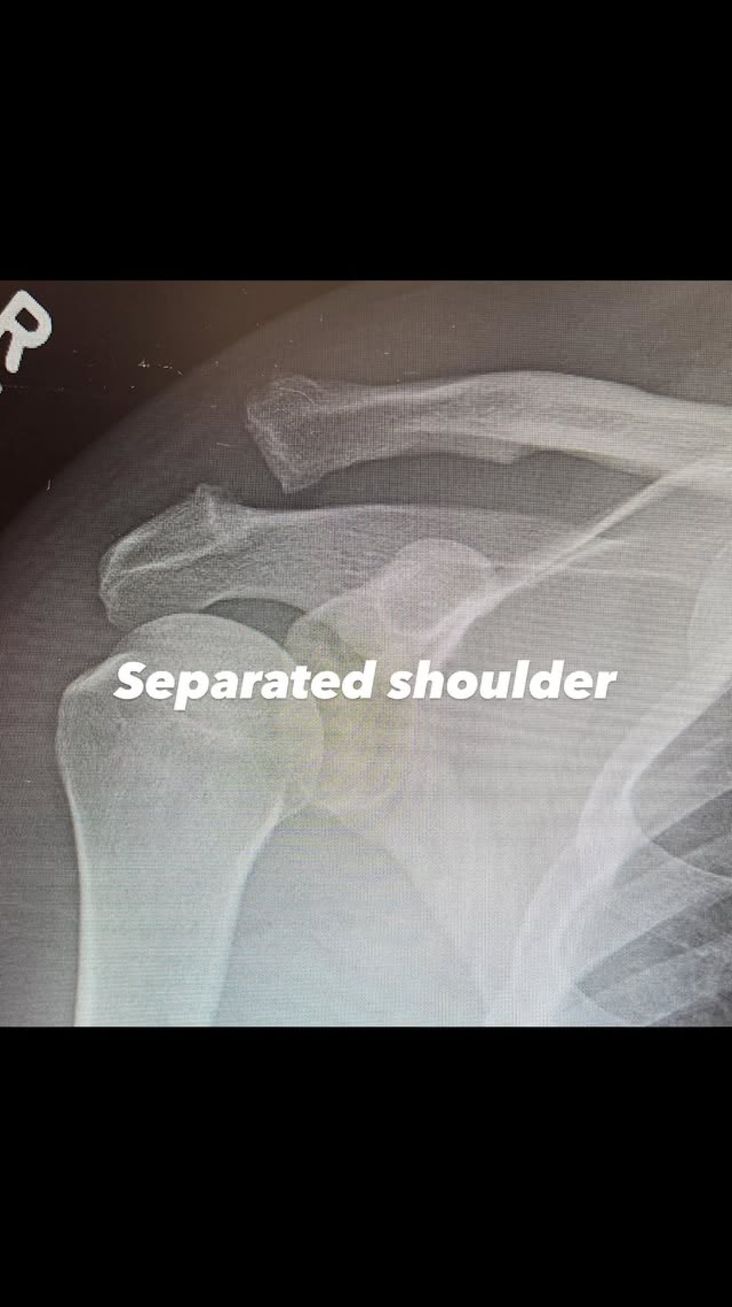

Kız arkadaşı Inka Williams, sosyal medya üzerinden Tatum'a mesaj göndererek, "Kocaman kötü kurt. Bunu başardık" diye yazdı. Bir çocuk babası olan Tatum, hastanede kalmasının nedenini açıklarken, omzunun röntgen görüntülerini paylaştı.

Röntgende iki kemiğin kırık olduğu açıkça görülüyordu. "Omuz çıkığı" diye yazan Tatum, ardından aynı bölgenin ameliyat sonrası ikinci bir fotoğrafını paylaştı.

Tatum, kemiklerini bir arada tutan büyük bir vidanın yerleştirildiği röntgenin altına, "Çivilenen omzum. Yaşasın!" diye yazdı. Tatum, yaralanmasının nasıl gerçekleştiğini açıklamadı, ancak ünlü oyuncu filmlerinde birçok tehlikeli sahneyi kendi başına yapmasıyla biliniyor.